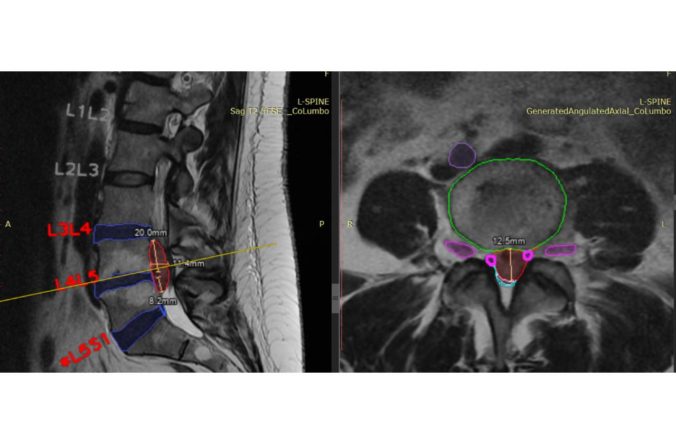

26.4.2023 (SITA.sk) – Unilabs, popredný poskytovateľ diagnostických služieb, nadviazal partnerstvo so spoločnosťou SmartSoft Healthcare s cieľom využiť jej riešenie CoLumbo, ktoré využíva umelú inteligenciu. Chce tak v Španielsku dosiahnuť zlepšenie popisovania a vyhodnocovania vyšetrenia driekovej chrbtice pomocou magnetickej rezonancie.

CoLumbo skracuje rádiológom čas popisovania a vyhodnocovania nálezom o 25 %, zvyšuje počet vyšetrených pacientov a zároveň zlepšuje presnosť diagnóz. Klinické testy dokázali, že CoLumbo môže znížiť počet chýb z opomenutia až o 15 %.

CoLumbo získal Pečať excelentnosti Európskej komisie. Projekt získal značku CE a je v súlade s reguláciami systémov kvality FDA. Má povolenie FDA 510(K), takže ho možno klinicky používať v Európe i v USA. Čaká sa aj na patent USPTO US 63/239,985.